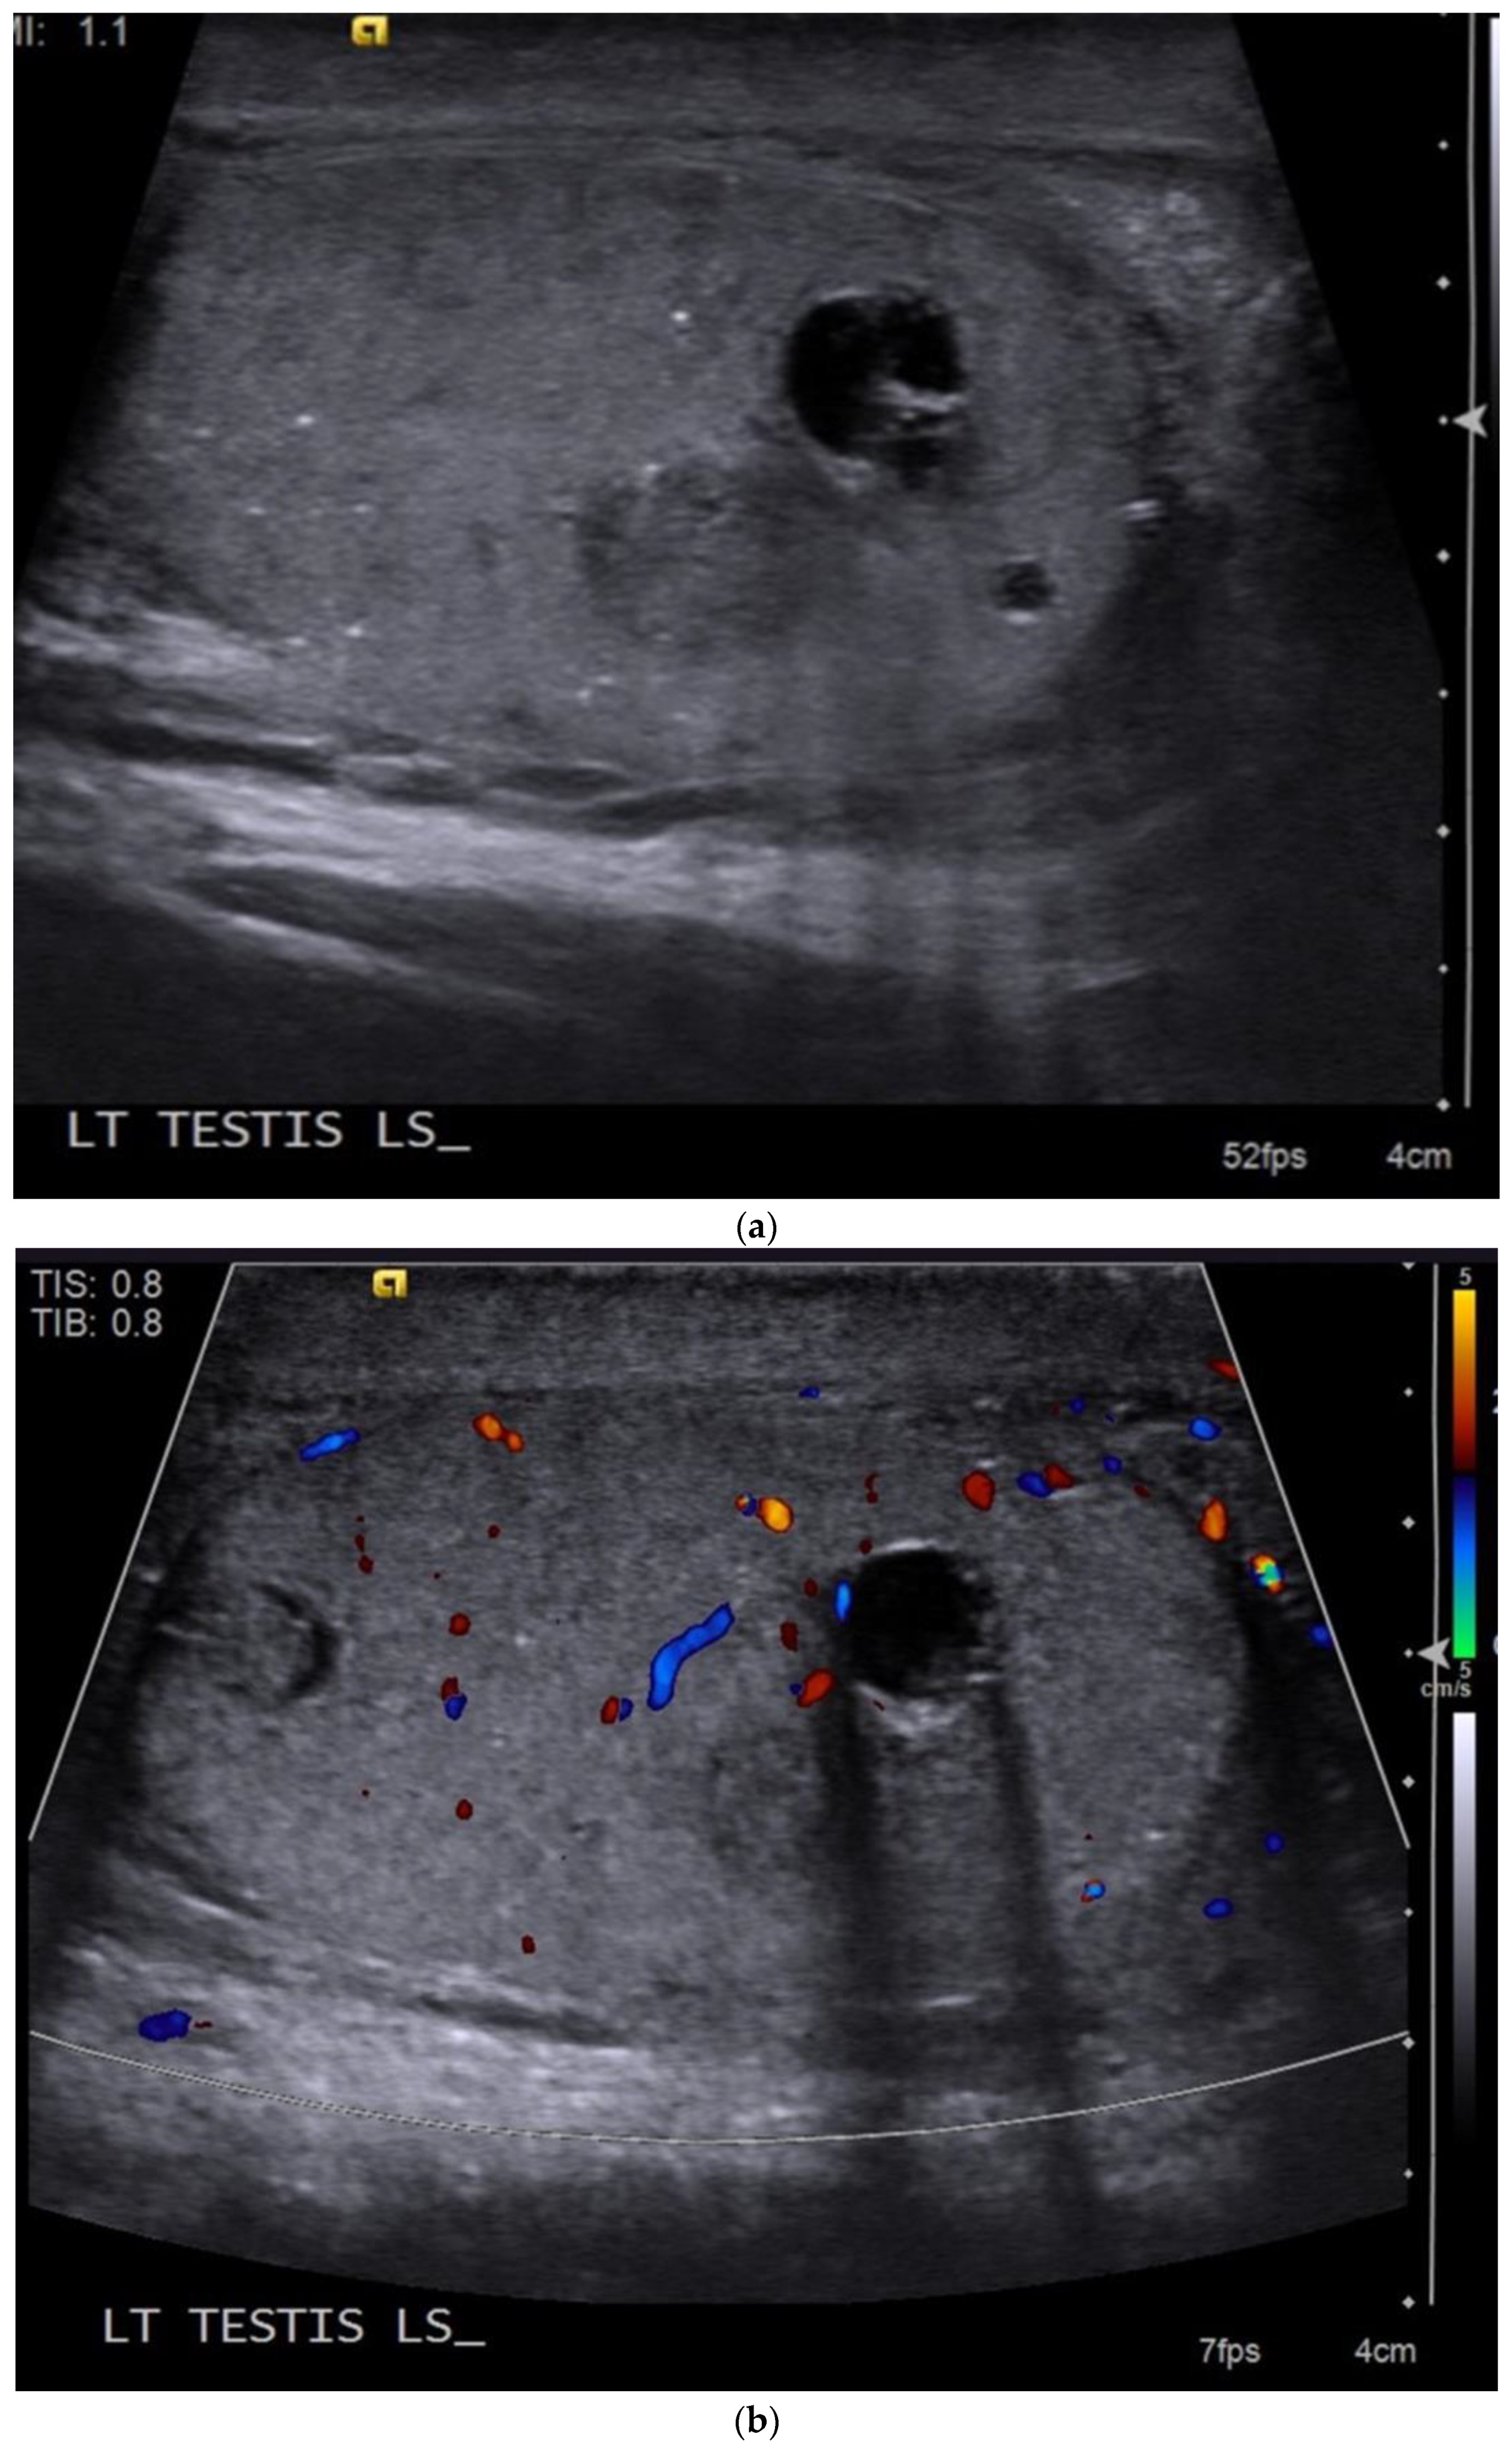

4.4. Teratoma

| Teratomas | Complex mass with well-defined borders Predominately cystic but can also contain macroscopic fat and calcifications |